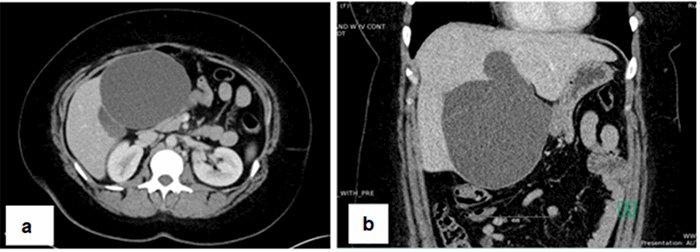

A CT A/P with contrast was significant for a large, hypoattenuating, multiloculated, exophytic, cystic mass in the left lobe that measured 12.6 x 11.6 x 9.9 cm, a marked increase in size from that on prior imaging, was compressing the adjacent gallbladder, duodenum, and stomach (Figure 1) still without any intra- or extrahepatic biliary dilatation. At that time, all liver enzyme levels were within normal limits.

Figure 1. a) Cross-sectional; and b) coronal imaging of mass, respectively.